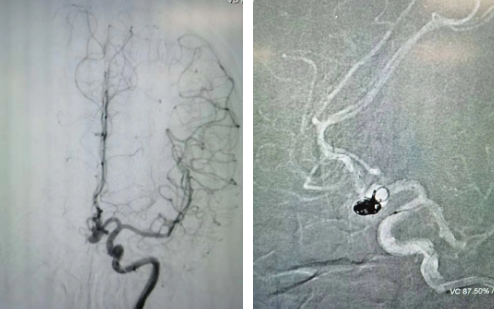

經(jīng)過全面仔細(xì)評估,西安國際醫(yī)學(xué)中心醫(yī)院神經(jīng)外科陸丹醫(yī)生決定采用微創(chuàng)介入進(jìn)行治療。在取得患者及家屬同意后,3月11日,陸丹醫(yī)生為患者行Atlas支架輔助顱內(nèi)動脈瘤栓塞術(shù)。

腦血管較外周血管更為脆弱、迂曲,對術(shù)者的操作技術(shù)及精準(zhǔn)性要求特別高。術(shù)中,陸丹醫(yī)生通過股動脈穿刺、置入微導(dǎo)管,再通過微導(dǎo)管將彈簧圏送入動脈瘤腔內(nèi),利用彈簧圈的機械閉塞作用,達(dá)到防止動脈瘤破裂的目的。術(shù)后,患者各項生命體征平穩(wěn)。

陸丹醫(yī)生介紹,此次腦科醫(yī)院首次采用Atlas支架輔助進(jìn)行顱內(nèi)動脈瘤栓塞術(shù)。以往動脈瘤栓塞術(shù)中的支架輸送導(dǎo)管較粗,支架順應(yīng)性差,易使載瘤動脈移位,而Atlas支架的輸送導(dǎo)管很細(xì),輸送順滑,同時順應(yīng)性及貼壁性強,能夠適應(yīng)迂曲的腦遠(yuǎn)端血管。